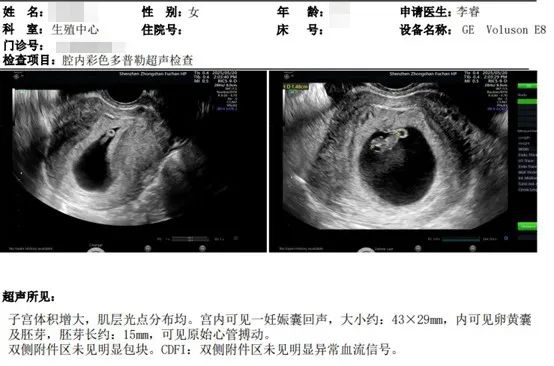

第二次移植(2025年4月):

• 强化免疫治疗(环孢素+双次阿托西班)

• HCG翻倍理想,B超显示胎心强劲,最终顺利度过孕早期!